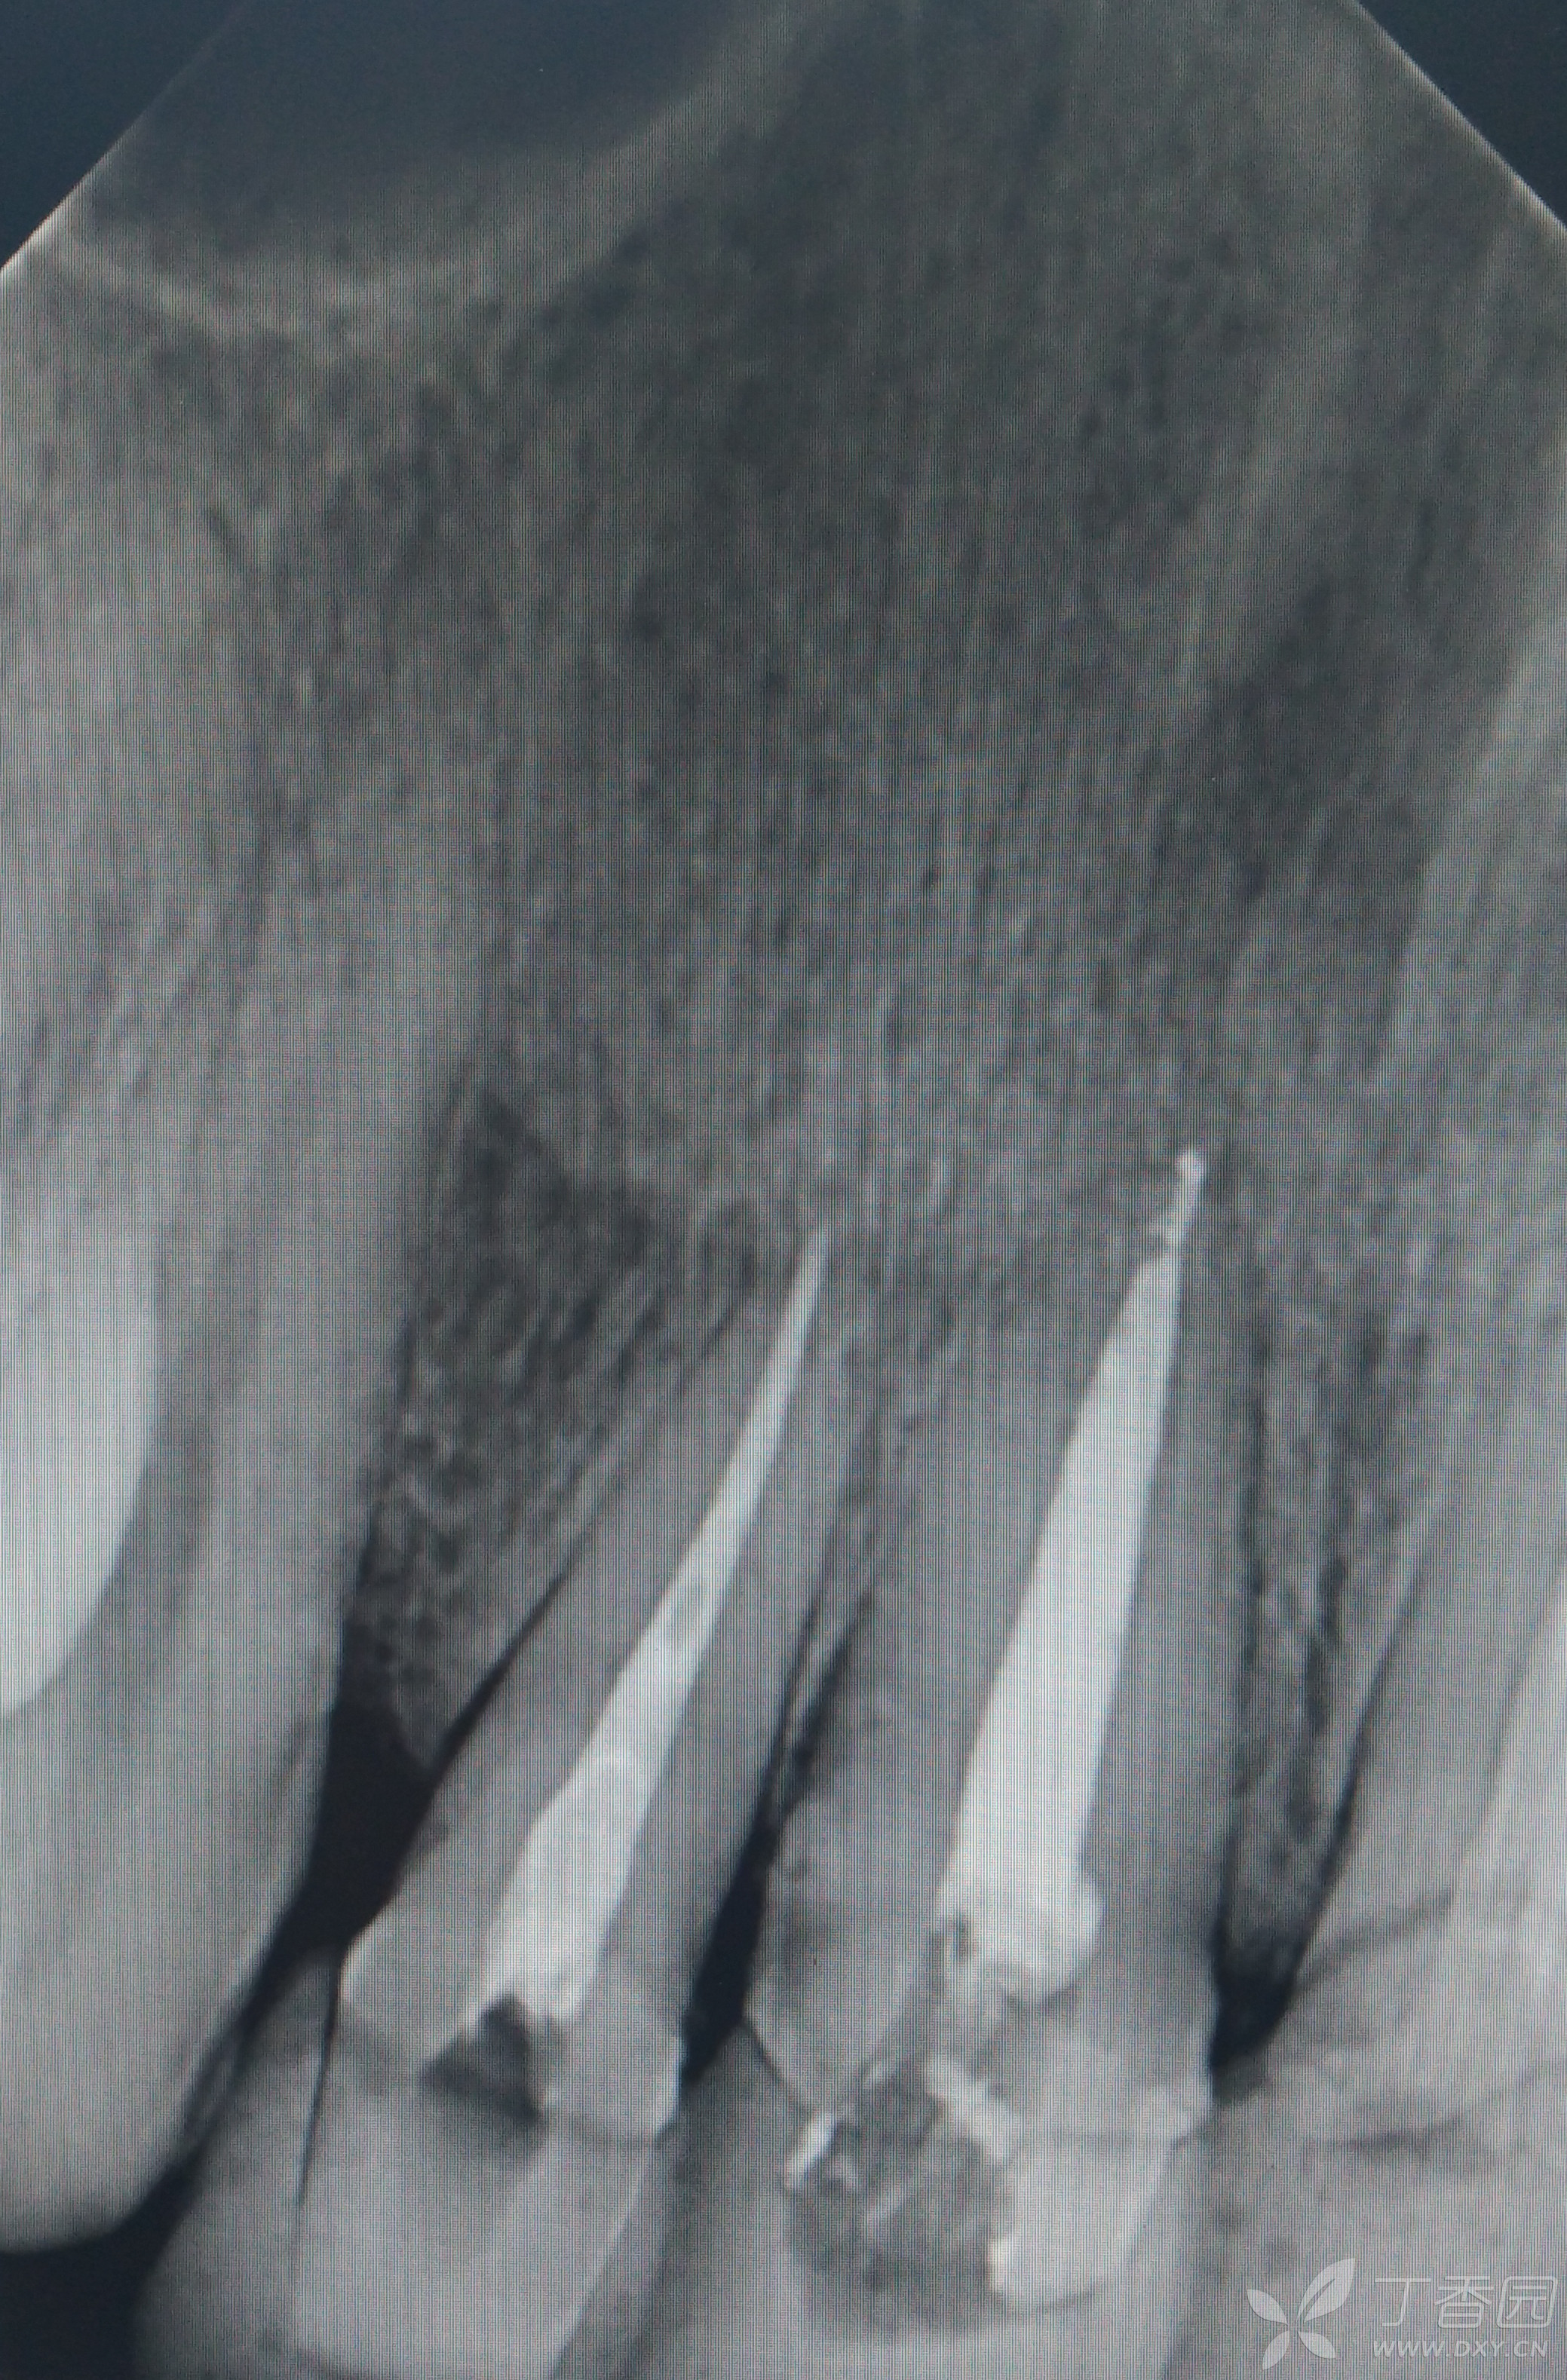

复杂根管治疗残冠根管治疗一例

左上后牙残冠显微根管再修复一例